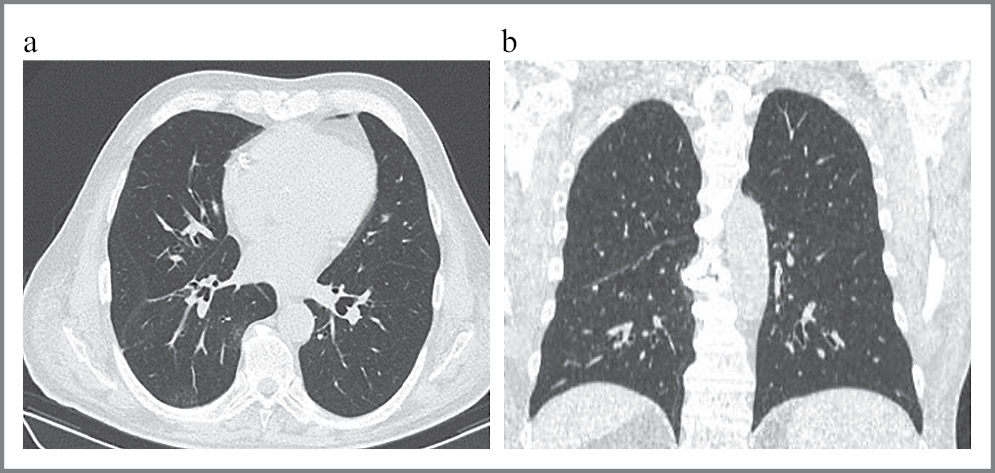

Выполнена повторная КТ легких через 16 дней, на которой определялись множественные очаговые инфильтративные изменения без динамики по сравнению с предыдущим исследованием (рис. 2, a, b).

Рис. 2: а – аксиальная проекция; b – фронтальная проекция. КТ легких первого пациента до операции. Отмечаются множественные участки затемнения по типу «матового стекла».

Проведены повторный забор и исследование биоматериала: РНК вируса SARS-CoV-2 не обнаружена.

В связи с такими неоднозначными данными проведен консилиум, в котором участвовали главный врач, эпидемиолог, анестезиолог, врачи-нейрохирурги. Так как данных в пользу коронавирусной инфекции не получено (отрицательные тесты на коронавирус, отсутствие антител), изменения в легких интерпретированы как следствие постоянной аспирации ликвора. Пациента госпитализировали в отдельную палату.